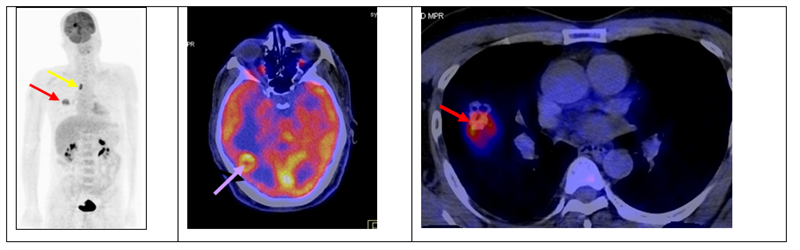

Ca lâm sàng 2: Bệnh nhân nam, 49 tuổi, chẩn đoán: Ung thư di căn não chưa rõ nguyên phát, chụp PET/CT để tìm tổn thương nguyên phát.

Hình 2: khối u ác tính phổi phải (mũi tên đỏ) di căn hạch (mũi tên vàng), di căn não (mũi tên tím). Giải phẫu bệnh sau chụp PET/CT là ung thư biểu mô tuyến.